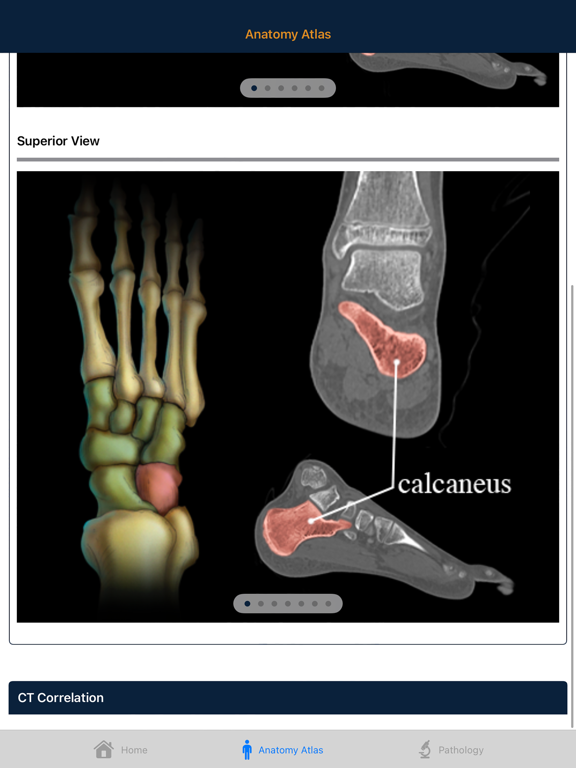

Understanding complex bony Anatomy and Pathology of the Foot and Ankle is essential to the interpretation of musculoskeletal CT. The anatomy of the ankle is complex and in the past CT evaluation of the ankle was often limited to axial slices and simple multiplanar reconstructions. However improvements in CT scanning technology now allow thin collimation and isotropic datasets. These advances along with easy to use 3D software have improved our ability to image the ankle with volume display. It is important for the radiologist to be familiar with the anatomy in all 3 dimensions.

This atlas aims to educate the radiologist with respect to normal and pathological anatomy through case studies and artist rendered interactive 3D models and illustrations. Radiology professionals will have a better understanding of ankle and foot bony anatomy after using this atlas.